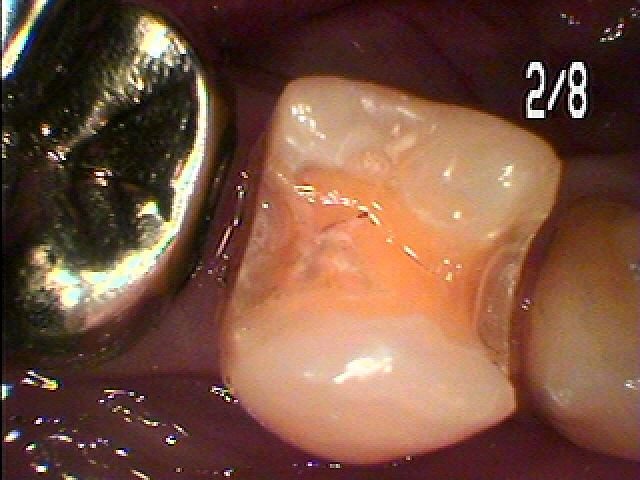

悪いところを除去していきました

セレックセラミックにて修復しています

昔のアマルガムが適合不良となっています